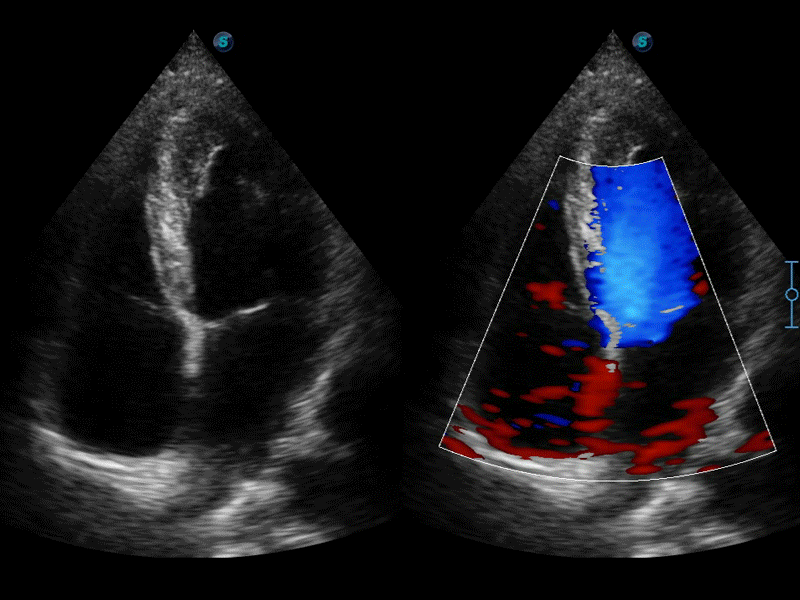

高分辨率血流成像技術(shù)提高了對(duì)低速血流信號(hào)的檢測(cè)能力。在提高空間分辨率的同時(shí),也克服了血流外溢現(xiàn)象,為用戶(hù)提供更加真實(shí)的血流動(dòng)力學(xué)信息。